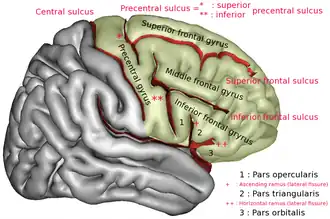

Superior frontal gyrus of the human brain | |

In neuroanatomy, the superior frontal gyrus (SFG, also marginal gyrus) is a gyrus – a ridge on the brain's cerebral cortex – which makes up about one third of the frontal lobe. It is bounded laterally by the superior frontal sulcus.[1]

The superior frontal gyrus is one of the frontal gyri.